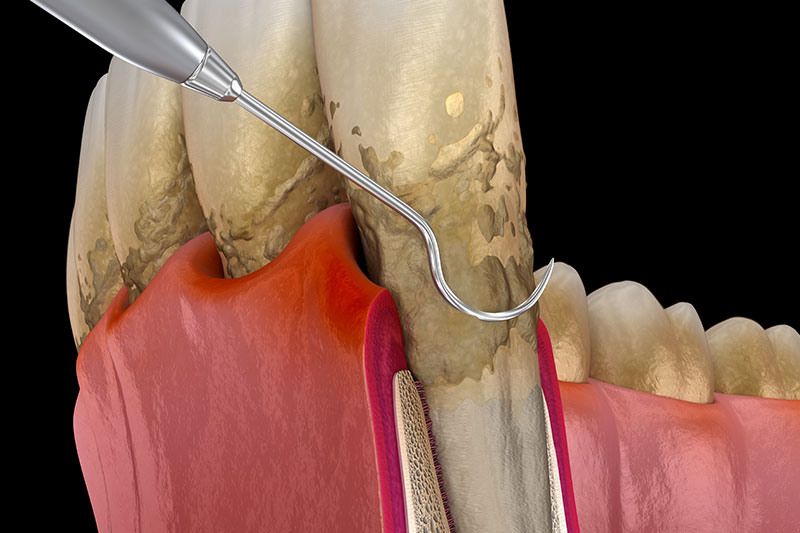

歯周基本治療(初期治療)

歯周基本治療は、歯周病の原因となる歯肉縁上・歯肉縁下の歯石を除去していきます。また、ブラッシング指導を行い、適切なブラッシングを習得していただきます。当院での治療と患者様のブラッシングが相乗効果となり、高い治療成果を生み出します。

歯周外科、歯周組織再生療法

歯周基本治療では取り切れない場所にある歯石を取るために、歯茎を切開し、目に見える状態で処置をします。また適応であればエムドゲインやリグロスといった再生誘導材料を用いた歯周組織再生療法を行い、失った骨を再生させる治療を行います。